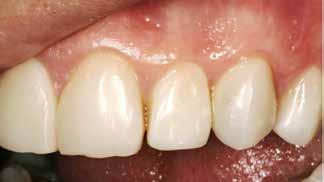

BAGGRUND – Denne kasuistik beskriver en patient, hvor der blev valgt protetisk behandling i ung alder.

PATIENTTILFÆLDE – En niårig pige havde stort behandlingsbehov og smerter fra tænderne på grund af tandudviklingsforstyrrelse. Der var flere gange forsøgt restaurering med komposit, som ikke fungerede. Laminater i feldspatkeram blev valgt for at fjerne mindst mulig tandsubstans, øge holdbarheden på restaureringerne og forbedre æstetikken. Patientens motivation, meninger og kooperationsevne var vigtige for behandlingsvalget, da behandlingen var tidkrævende og til tider udmattende for en ung patient.

KONKLUSION – Resultatet var vellykket og medførte forbedret livskvalitet. Protetisk behandling med adhæsiv teknik kan være et godt behandlingsalternativ for børn og unge på ret indikation.

VED BEHOV FOR OMFATTENDE TANDRESTAURERING HOS BØRN OG UNGE kan flere behandlingsalternativer være aktuelle (1). Restaurering med fyldningsmaterialer er som regel førstevalg, men i nogle tilfælde fungerer dette ikke godt nok. Ved udarbejdelse af behandlingsplan må klinikerne kende til mulige behandlingsalternativer og vurdere disse på baggrund af kliniske fund, patientens symptomer og kooperationsevne samt patientens ønsker og planlægge behandling i et livsløbsperspektiv.

PATIENTTILFÆLDE

Beskrivelse af patienten Patienten blev henvist til specialistuddannelsen i pædodonti ved Universitetet i Oslo, da hun var syv år gammel, for diagnostik og behandling af tandudviklingsforstyrrelse i primære og permanente tandsæt. Pigen havde pollenallergi, var ellers sund og rask og havde intet medicinforbrug.

Klinisk undersøgelse viste emaljehypoplasier og hypomineralisering på 1+, +1, 2-, 1-, -1 og -2 (Fig.1). Hun havde Angle klasse II, pladsmangel i begge kæber og agenesi af -5. Der var isninger ved spisning og tandbørstning. Fundene var forenelige